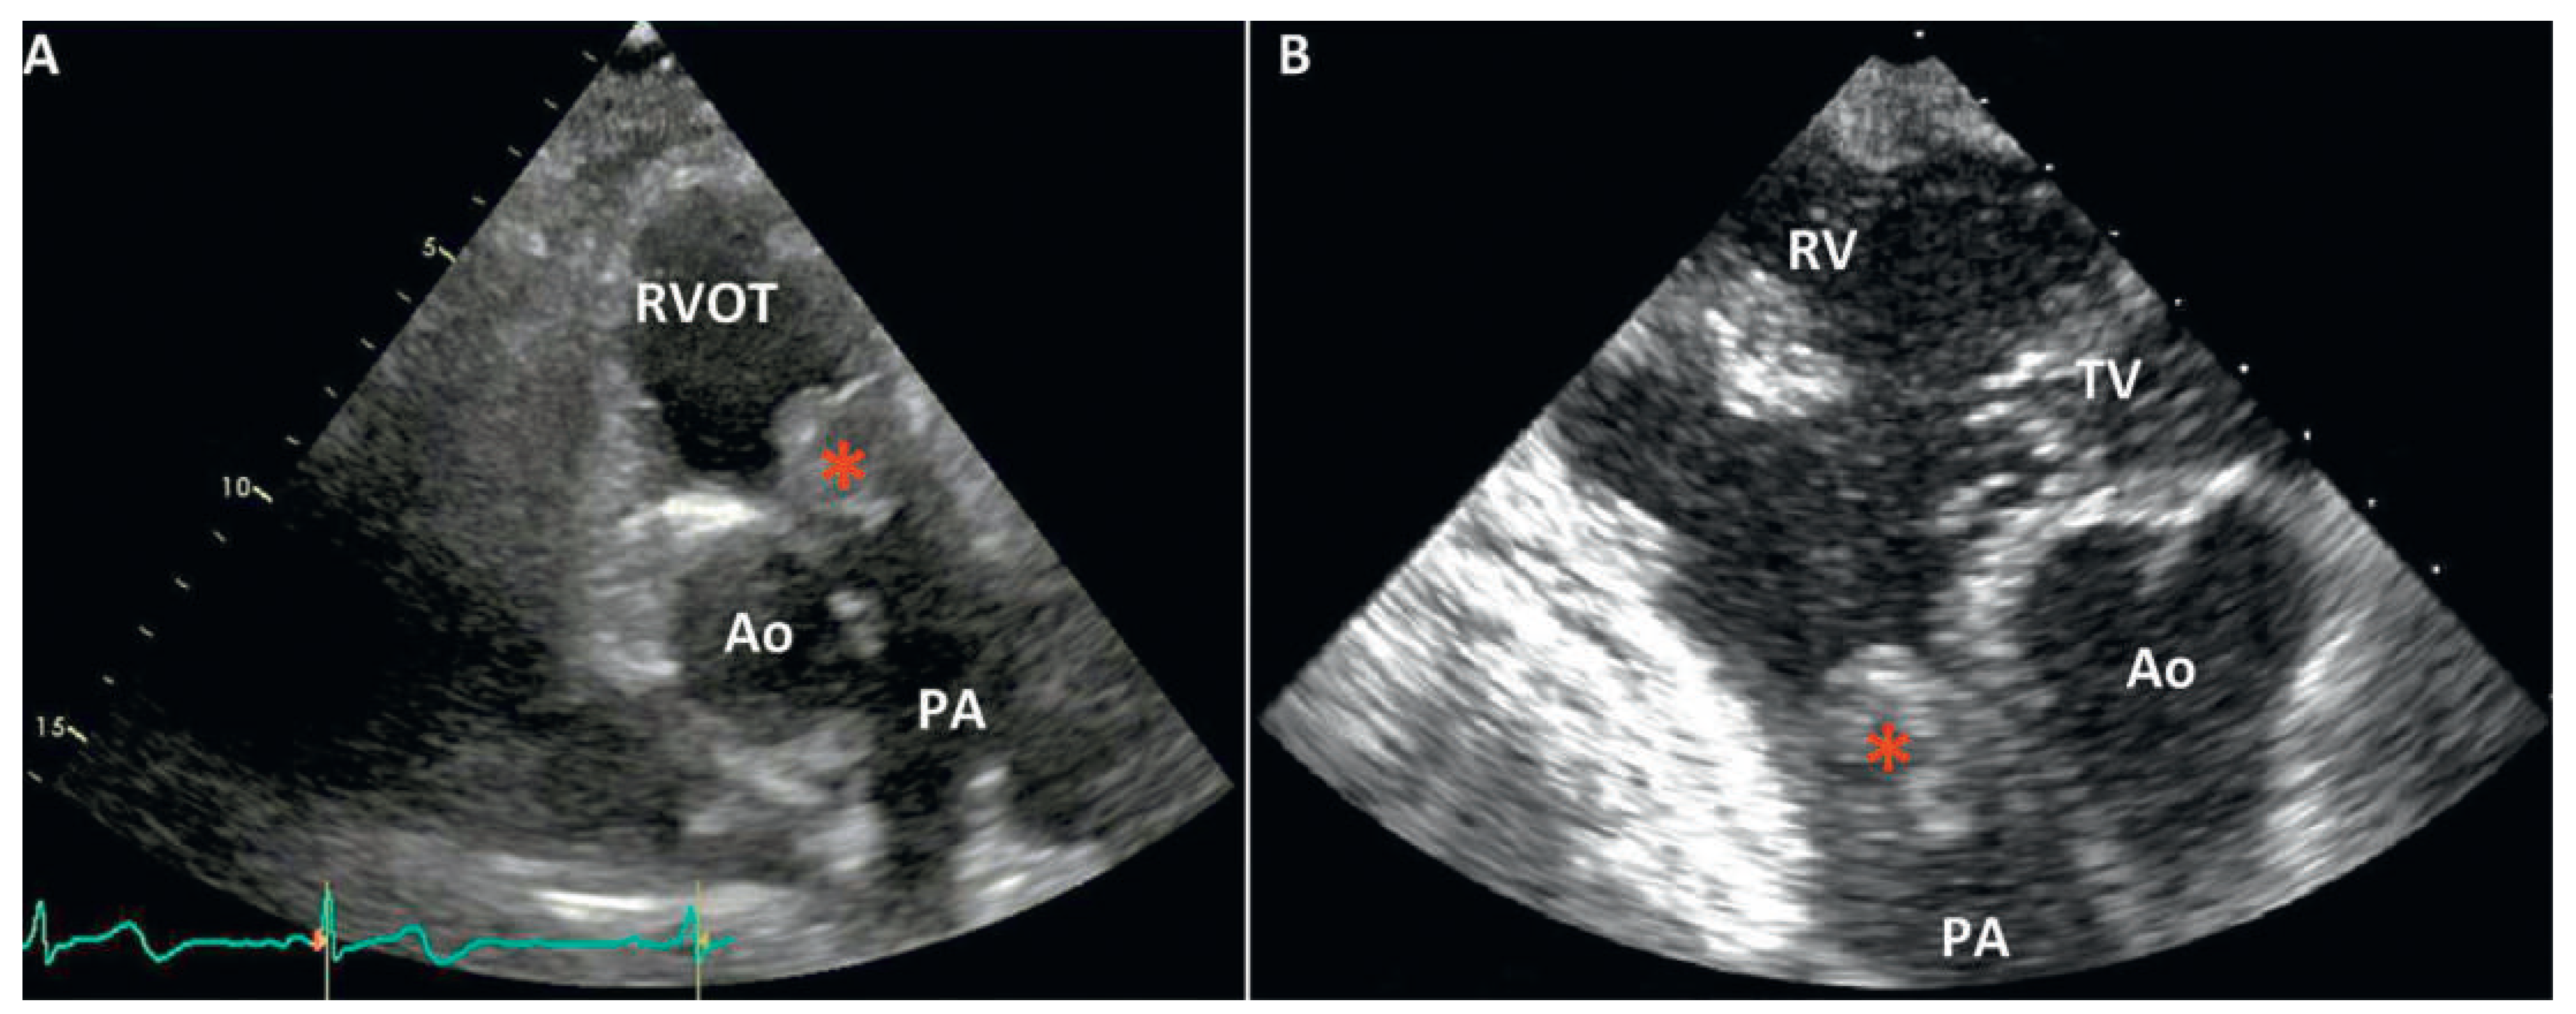

Transthoracic echocardiography (TTE) revealed a moderate pulmonary valve stenosis caused by a globular mass protruding into the right ventricular outflow tract (RVOT) during diastole (Figure 1). The maximum pulmonary pressure gradient was measured at 42 mm Hg (mean 30 mm Hg). Left as well as right ventricle size and function were normal.

Figure 1. (A) TTE parasternal long axis view of the pulmonary artery. The tumour is recognised as a large round mass invading the pulmonary valve. (B) Transoesophageal echocardiography (TOE) in transgastric inflow–outflow view of the right ventricle. The tricuspid valve and the right ventricular apex are seen at the top of the picture. The pulmonary valve is replaced by a ball-like tumour (*) obstructing the RVOT. Ao = aorta; PA = pulmonary artery; RV = right ventricle; RVOT = right ventricle outflow tract; TV = tricuspid valve.